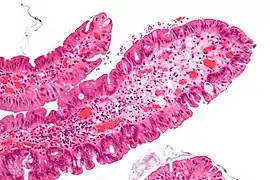

Traditional serrated adenomas are characterized by ectopic crypts, pseudostratification, and a villous pattern with stretched nuclei.[4]